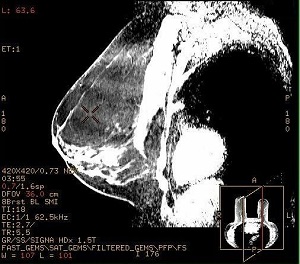

Figure 2. Ripple-like artifact in sagittal reformat from axial source scan data